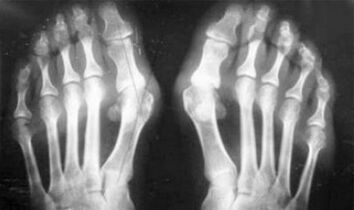

- Joint deformation occurs;

- The joints are deformed and their mobility decreases.

As you can see, the differences in symptoms are trivial: in both cases, pain, stiffness, and fatigue.Arthritis and arthritis can affect different joints in the human body.Osteocartilage can form due to damage to the spine and discs - similar to arthritis.According to the location of the disease, distinguish ankle joints, shoulders, hip joints, etc.